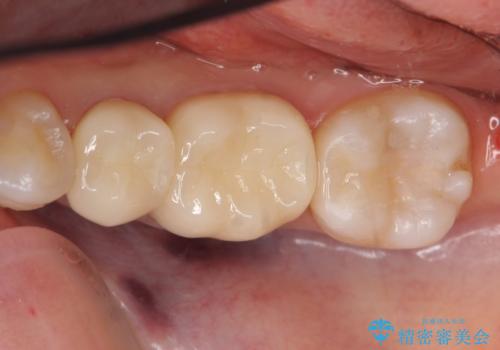

左下7はセラミックインレーによる修復を行い、左下5、6はオールセラミッククラウンによる補綴を行いました。

オールセラミッククラウンについて

今回用いたオールセラミッククラウンはジルコニアフレームという白い素材の上にセラミックを盛っているため、審美性が非常に高いのが特徴です。

また、ジルコニアは人工ダイヤモンドの材料にも使われているほど高い強度を持っており、そのためオールセラミッククラウンは審美性だけでなく、奥歯やブリッジの補綴も可能とするクラウンです。

セラミックインレーについて

当院のセラミックインレーはemaxという強度と審美性に優れた材料を使用しています。

またプレス方式でインレーを製作しているため、削り出しで製作するCADCAMより優れた適合性も持ち合わせており、虫歯が再発しにくい修復物です。